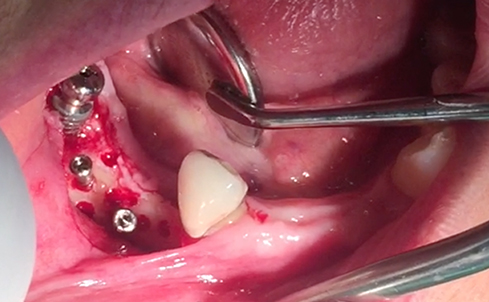

Implants/Bone Grafting

Partial edentulous clinical cases